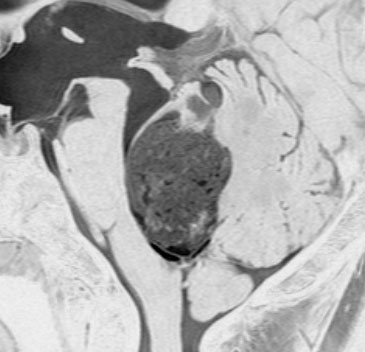

左は脳幹部腫瘍(退形成性神経節膠腫),右は小脳腫瘍(毛様細胞性星細胞腫)です。どちらも第4脳室を埋め尽くすように発育しています。これらはどちら側から発生したかが明瞭な例ですが,第4脳室腫瘍の中には脳幹部からか小脳からか解らないものもあります。でも多くは小脳側からです。脳幹部側からで注意しなければならないのは上衣腫と血管芽腫です。